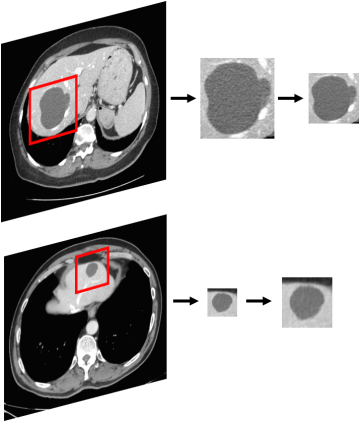

Figure 1 shows examples of the input data and the ROI extraction process. The dataset was made up of 182 portal-phase 2-D CT scans (Figure 1a): 53 cysts, 64 metastases, 65 hemangiomas. An expert radiologist marked the margin of each lesion and determined its corresponding diagnosis which was established by biopsy or a clinical follow-up. This serves as our ground truth.

Liver lesions vary considerably in shape, contrast and size (10 - 102mm). They also vary within categories. In addition, they are located in interior sections of the liver or near its boundary where the surrounding parenchyma tissue of the lesions changes. Each type of lesion has its own characteristics: Cysts are non-enhancing water-attenuation circumscribed lesions. Metastases are hypoattenuating, have soft-tissue attenuation and less well-defined margins than cysts, and hemangiomas show typical features of discontinuous nodular peripheral enhancement, with fill-in on delayed images [31]. Despite this detailed description, some characteristics may be confusing, in particular for metastasis and hemangioma lesions (see Figure 1a). Metastases can contain areas of higher density, probably prominent blood vessels or calcifications that can be mistaken for hemangiomas attributes. Hemangiomas are benign tumors and metastases are malignant lesions derived from different primary cancers. Thus, the correct identification of a lesion as metastasis or hemangioma is especially important.

The input to our classification system are ROIs of lesions cropped from CT scans using the radiologist’s annotations. The ROIs are extracted to capture the lesion and its surrounding tissue relative to its size. Due to the large variability in lesion sizes, this results in varying size ROIs (Figure 1b).

Figure 1: (a) Dataset examples of cyst, metastasis and hemangioma liver lesions. (b) ROI extraction process from a 2-D CT slice of the liver. All ROIs are resized to a uniform size.